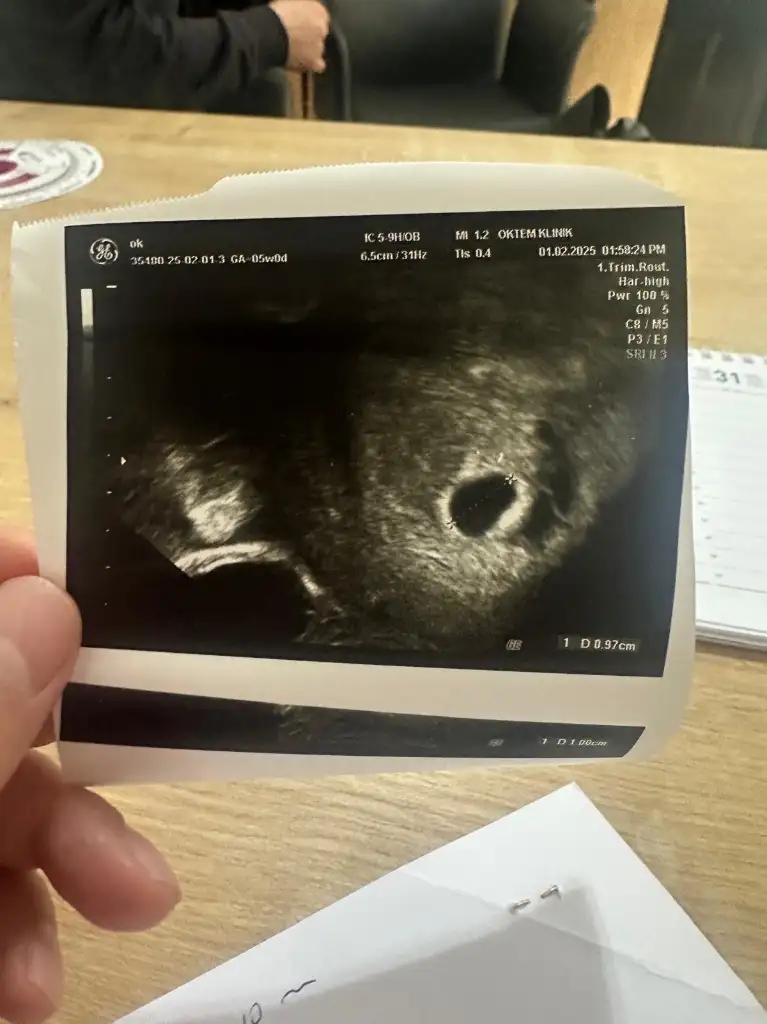

Selamünaleyküm canm öncelikle hiç korkma bisi olmuyor o bende de vardı bisi olmuyor yani 12. Haftada falan kayboldu kese büyüdükçe kayboluyor bana hatta progestan vermişti doktorum o bana yan etki yaptı bıraktım ama yine de kayboldu 5 gün kullanabildim sadece ama merak etme gidiyor sadece dikkat et9 haftalık hamileyim 5.haftanın sonunda bebeği ve kalp atışını görmüştük o gün kanama alanı tespit edildi doktor progestan fitil başlattı bugün kontrolüm vardı kanama alanı hala duruyor bebek sağlıklı görünüyor çok şükür doktor büyümemişte küçülmemişte ama yok olmadığı sürece her zaman riskli dedi benim dışarıdan bir kanamam lekelenmem olmadı şükür ki ama sürekli risk denmesi çok tedirgin ediyor bu süreci yaşayanlar varsa bilgi almak isterim 12. 16.haftaya kadar kaybolabilir o zamana kadar risk var diyeceğim dedi doktor ama benim düşüncem bir şey olmaz diyor ultrason fotoğrafını da ekliyorum

Benim 4 gebeliğimde de vardı kan sulandırıcı iğne ve ilaç kullanıyorsanız birinin kesilmesi gerek9 haftalık hamileyim 5.haftanın sonunda bebeği ve kalp atışını görmüştük o gün kanama alanı tespit edildi doktor progestan fitil başlattı bugün kontrolüm vardı kanama alanı hala duruyor bebek sağlıklı görünüyor çok şükür doktor büyümemişte küçülmemişte ama yok olmadığı sürece her zaman riskli dedi benim dışarıdan bir kanamam lekelenmem olmadı şükür ki ama sürekli risk denmesi çok tedirgin ediyor bu süreci yaşayanlar varsa bilgi almak isterim 12. 16.haftaya kadar kaybolabilir o zamana kadar risk var diyeceğim dedi doktor ama benim düşüncem bir şey olmaz diyor ultrason fotoğrafını da ekliyorum

Merhabalar naptınız acaba bende aynı durumu yaşıyorum kanama alanım var benim 11+4 te kanamam oldu Suan lekelenmelerimde devam ediyor kahverengi çok korkuyorum yarında randevum var insallah hayırlı sonuclar alırım9 haftalık hamileyim 5.haftanın sonunda bebeği ve kalp atışını görmüştük o gün kanama alanı tespit edildi doktor progestan fitil başlattı bugün kontrolüm vardı kanama alanı hala duruyor bebek sağlıklı görünüyor çok şükür doktor büyümemişte küçülmemişte ama yok olmadığı sürece her zaman riskli dedi benim dışarıdan bir kanamam lekelenmem olmadı şükür ki ama sürekli risk denmesi çok tedirgin ediyor bu süreci yaşayanlar varsa bilgi almak isterim 12. 16.haftaya kadar kaybolabilir o zamana kadar risk var diyeceğim dedi doktor ama benim düşüncem bir şey olmaz diyor ultrason fotoğrafını da ekliyorum

Ne durumdasınız? Benim 11. Hafta yoğun kanamam olmuştu şimdi 17. Haftada lekelenmem devam ediyor evde yatıyorum.9 haftalık hamileyim 5.haftanın sonunda bebeği ve kalp atışını görmüştük o gün kanama alanı tespit edildi doktor progestan fitil başlattı bugün kontrolüm vardı kanama alanı hala duruyor bebek sağlıklı görünüyor çok şükür doktor büyümemişte küçülmemişte ama yok olmadığı sürece her zaman riskli dedi benim dışarıdan bir kanamam lekelenmem olmadı şükür ki ama sürekli risk denmesi çok tedirgin ediyor bu süreci yaşayanlar varsa bilgi almak isterim 12. 16.haftaya kadar kaybolabilir o zamana kadar risk var diyeceğim dedi doktor ama benim düşüncem bir şey olmaz diyor ultrason fotoğrafını da ekliyorum

Benim de kanama alanı var şuan bebek 5 haftalık. Kese göründü ama yolk sac görünmedi9 haftalık hamileyim 5.haftanın sonunda bebeği ve kalp atışını görmüştük o gün kanama alanı tespit edildi doktor progestan fitil başlattı bugün kontrolüm vardı kanama alanı hala duruyor bebek sağlıklı görünüyor çok şükür doktor büyümemişte küçülmemişte ama yok olmadığı sürece her zaman riskli dedi benim dışarıdan bir kanamam lekelenmem olmadı şükür ki ama sürekli risk denmesi çok tedirgin ediyor bu süreci yaşayanlar varsa bilgi almak isterim 12. 16.haftaya kadar kaybolabilir o zamana kadar risk var diyeceğim dedi doktor ama benim düşüncem bir şey olmaz diyor ultrason fotoğrafını da ekliyorum